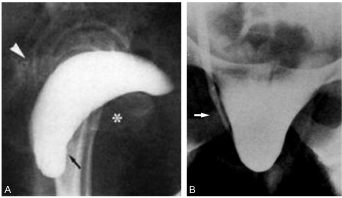

Fig. 29.1. Cystocèle. Cystographie descendante.

Profil debout avec effort de poussée (A) : aspect caractéristique de bascule postérieure de la vessie (tête de flèche) avec une descente du col vésical (flèche) par rapport à la symphyse pubienne (∗). Face debout avec effort de poussée (B) : incarcération de l’uretère pelvien droit (flèche) avec dilatation sus-jacente.

Source : CERF, CNEBMN, 2022.